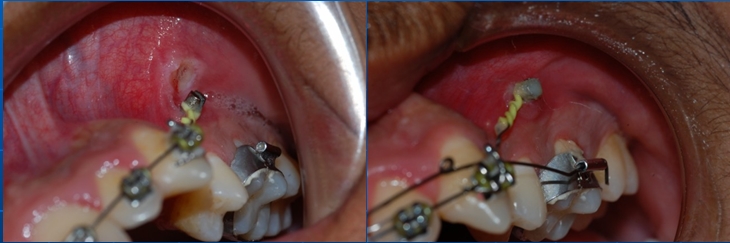

See below how the ulceration was caused and it healed after covering screw head with composite, lower image shows ulceration in lower arch,

failure as well as ulceration is more in mandible in this area compared to maxillary arch.

See below how the ulceration was caused and it healed after covering screw head with composite, lower image shows ulceration in lower arch,

failure as well as ulceration is more in mandible in this area compared to maxillary arch.